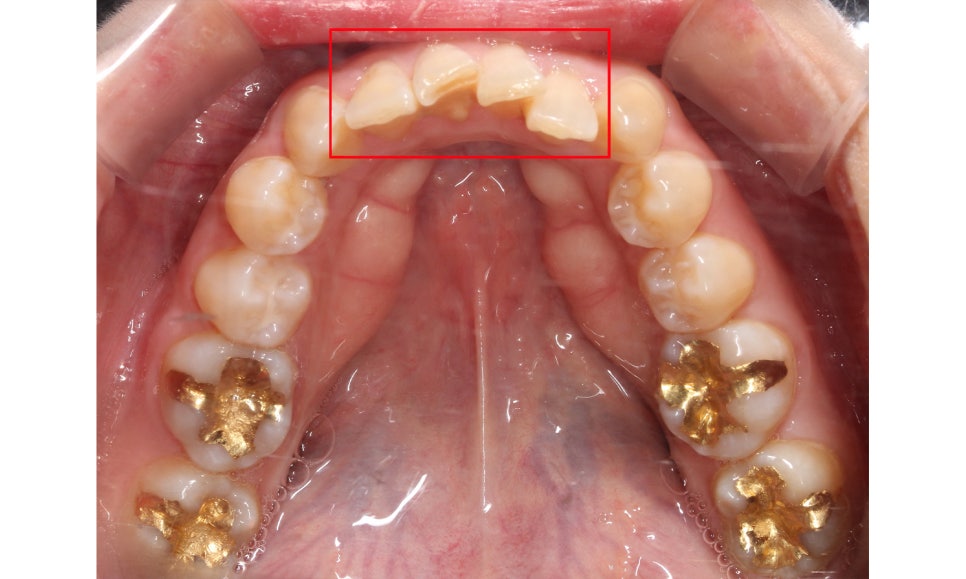

양악교정 전 치아의 교합평면 모습을 보면

송곳니교정을 하지 않아 견치의 높이가

상당히 올라가 있는 모습입니다.

송곳니교정 후 교합평면 사진을 보면

송곳니가 변위된 모습을 확연하게

확인할 수 있는 모습으로 표시된 부분의

잇몸 라인이 수평적으로 균일하게

바뀐 모습입니다.

양악교정 후 상악 교합면을 보시면

치아의 배열이 U자에 가까운 모습으로

바뀐 것을 확인할 수 있는데요,